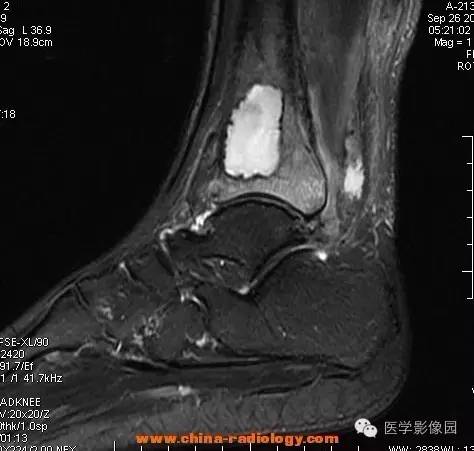

影像学表现:胫骨中下段干骺端不未规则形长T1长T2信号,T2WI见不完整环形稍低信号影,T2脂肪抑制低信号更明显,并见胫骨下段及踝关节后外侧软组织呈弥漫稍高信号,增强明显不均匀强化,增强见低信号环内有环形强化影。

影像学表现:表现为长骨干骺端有椭圆形密度减低区,边缘有清晰的骨质硬化,病变与邻近正常骨髓腔境界清楚。MRI上T1WI呈低信号,少数呈等信号,T2WI多为混杂高信号,增强扫描可见环状强化,强化的脓肿壁薄而均匀。